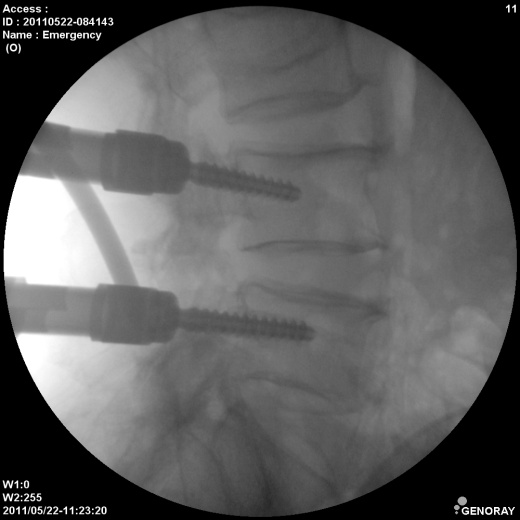

Аппарат применяется в различных областях медицины, таких как хирургия, ортопедия, педиатрия, травматология, урология и многих других. «РЕНЕКС-ОПТИМАЛ» имеет широкий диапазон перемещения и легко позиционируется во всех направлениях.

В качестве приемника используется усилитель рентгеновского изображения (УРИ) с ПЗС-матрицей 1024х1024 пикселей. Мощность рентгеновского питающего устройства 5,3 кВт. Система принудительного воздушного охлаждения, позволяет эффективно использовать аппарат на протяжении долгого времени без перегрева. Широкий диапазон регулирования количества импульсов при импульсной рентгеноскопии позволяет значительно снизить лучшею нагрузку, при этом при необходимости возможно проводить исследования с частотой до 30 кадров в секунду. С-дуга оснащена интерактивной сенсорной панелью управления всеми параметрами исследования на штативе аппарата.

- Непрерывная и импульсная рентгеноскопия с цифровой обработкой изображения.

- Цифровая рентгенография.